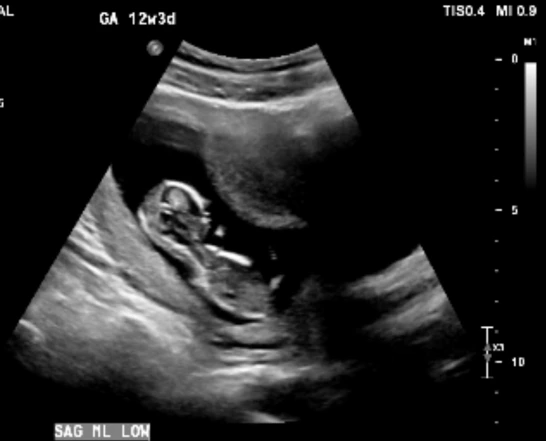

주변에 아이가 생기지 않아 고생하는 사람들을 보긴 했지만 남의 일이라는 생각이 컸고, 자연임심으로 아이들을 낳은 친구들이 더 많았기에 나도 피임을 하지 않으면 어렵지 않게 아이가 생길 거라고 생각했다. 그러나 한 달 두 달이 지나도 소식이 없자 자연임신이라는 것이 쉬운 게 아니라는 것을 깨달았고 좀 더 집중해서 아이를 갖으려 노력한 결과, 세 달째가 됐을 때 마법처럼 생리가 멈추었다. 임신테스트기에 두 줄을 확인했을 때 심장이 두근거리고 호흡이 빨라졌다. 진짜인가 싶어 한동안 두줄을 뚫어져라 쳐다보고 있었다. 마이클은 이 소식을 듣고는 나를 안아주며 너무 좋다고 기뻐했다. 임신을 하고 나서 처음 몇 주 동안은 실감이 전혀 나지 않다가 12주 차 초음파에서 아기의 심장소리를 듣고 그제야 내 뱃속에 생명이 자라고 있다는 것을 느낄 수 있었다. 구토를 하는 입덧은 없었지만 4시간에 한 번씩 밥을 먹어야만 메슥거림이 줄어들었고 소화가 너무 안 돼서 항상 위가 불편했다. 먹지 않아도 메슥거리고 그렇다고 먹으면 또 소화가 안 돼서 아프고, 이도저도 하기 힘든 상태가 2달가량 지속됐다.

도시 이동을 해서 남편과 둘만 사는 보금자리로 이사를 가면서 입덧도 함께 사그라들었다. 내 집에서 일도 안 하고 내가 마음 편하게 있을 수 있다는 것 자체로 최고의 태교를 할 수 있었다. 영양제도 꾸준히 챙겨 먹고 가능하면 건강한 음식을 먹으려고 노력했다. 로토루아에는 맛있는 식당도 없고 제대로 된 한국 마트 없었기에 밥을 먹는 것에 어려움이 있신 했으나 한국에 갈 날만 손꼽아 기다리며 한 끼 한 끼를 버텼다. 20주가 넘어가면서 배가 조금씩 더 부르기 시작했고 27주 차에는 배가 상당히 나온 상태로 한국을 방문했다. 12시간 비행에 걱정을 많이 했으나 다행히 한국이 겨울이라 그런지 비행기에는 사람이 많이 차지 않아 누워서 올 수 있었다. 긴 비행으로 지친 몸을 이끌고 출구에 나오자 마중 나온 부모님이 우리를 기다리고 있었다. 여름옷을 입고 온 우리는 나름 패딩을 챙겨서 입긴 했지만 한국 1월 강추위에 주차장까지 걸어가는 그 짧은 순간 사이에 정말 너무 추워서 온몸이 부들부들 떨렸다.